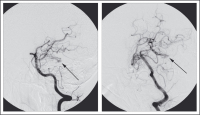

Abbildung 3: Transfemorale cerebrale Panangiographie am 8. postoperativen Tag: Initialer Verdacht auf arteriovenöse Malformation (AVM) bestätigt.

Panangiographie